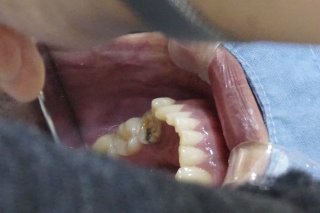

나이가 들면서 치아가 약해지면 음식을 제대로 씹지 못하거나 발음이 부정확해져 불편을 겪는 경우가 많습니다. 그러나 임플란트 시술은 비용이 높아 쉽게 결정하지 못했던 것이 사실입니다. 많은 어르신들이 경제적 부담 때문에 필요한 치료를 미루고 있으며, 그로 인해 영양 불균형이나 자신감 상실로 이어지기도 합니다.

임플란트 건보 지원은 만 65세 이상 건강보험 가입자 또는 피부양자가 대상입니다. 단, 완전 무치악 환자는 제외되며 일부 치아가 남아 있어야 합니다. 어금니와 앞니 모두 지원 대상에 포함되며, 평생 최대 두 개까지 적용됩니다.